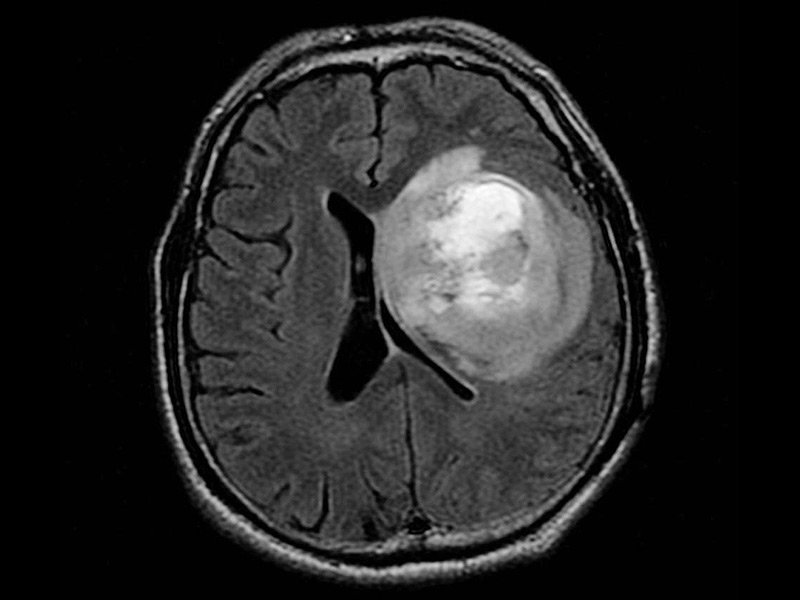

神經膠質瘤 是在中樞神經系統(tǒng)的神經膠質細胞中形成的腦癌或腦腫瘤。膠質細胞是圍繞并支持神經細胞的那些。一些腦癌起源于身體其他部位,而神經膠質瘤則起源于中樞神經系統(tǒng),通...

神經膠質瘤是在中樞神經系統(tǒng)的神經膠質細胞中形成的腦癌或腦腫瘤。膠質細胞是圍繞并支持神經細胞的那些。一些腦癌起源于身體其他部位,而神經膠質瘤則起源于中樞神經系統(tǒng),通常被稱為“原發(fā)性”腦瘤。腦膠質瘤的治療方法有哪些?相關閱讀:8歲女孩5cm較大基底節(jié)區(qū)腦瘤成功切除記,除了其起源的位置以外,神經膠質瘤還具有許多特征。惡性神經膠質瘤的一個重要特征是它們沒有清晰可辨的界限或“彌漫性”。即使被去除,部分神經膠質瘤也經常殘留并導致復發(fā)。雖然神經膠質瘤不會擴散到中樞神經系統(tǒng)之外,但在疾病的復發(fā)階段,通常會在整個腦干中發(fā)現(xiàn)多個神經膠質瘤。

膠質瘤

超過97%的腦膠質瘤較嚴重兒童(彌漫性橋腦膠質瘤)在三年內死亡。神經膠質瘤在兒童中不成比例地普遍存在,它們是年輕人中癌癥死亡的二大原因。然而,不同形式的神經膠質瘤有不同的預后和治療方法。超過97%的腦膠質瘤較嚴重兒童(彌漫性橋腦膠質瘤)在三年內死亡。

腦膠質瘤的治療方法有哪些?隨著新療法、影像學技術的發(fā)展以及對中樞神經系統(tǒng)腫瘤生長過程的深入研究,人們對中樞神經系統(tǒng)惡性腫瘤的治療熱情越來越高。盡管進行了的研究和治療腦癌,但大多數患者的臨床結果仍然令人沮喪。對多種腫瘤亞型、行為和結果的認識使人們對治療膠質瘤的個體化藥物產生了興趣。這種新的范式要求在診斷時對腫瘤表型進行評估,以便針對每個患者進行針對性的治療。研究涉及干細胞、納米技術和分子醫(yī)學的新療法將為膠質瘤患者提供多樣化的治療選擇。

手術治療是膠質瘤治療的中心力量

腦膠質瘤的外科手術,主要以減少腫瘤細胞數量,減少腫瘤負荷,減輕顱腔壓力,減除神經功能缺失為目的。目前的膠質瘤手術,已經進入了一個微創(chuàng)時代,與前相比,更為順利,創(chuàng)傷更為小,腫瘤切除更為完全。顯微鏡應用于腦膠質瘤的切除,可以更加清晰地辨別腫瘤與腦組織的邊界,以及周圍重要的神經血管等結構,從而能夠在順利的情況下,較大化地切除膠質瘤。神經導航的應用,將膠質瘤的手術切除,提高到新的高度。神經導航與汽車導航相類似,可以使外科醫(yī)生在手術前從切口的設計、術中功能腦區(qū)的辨認以及手術切除方式的選擇等方面,更加精確和細化。

在一份關于報道69例實施顯微手術治療的膠質瘤患者臨床資料顯示,69例患者腫瘤全切除56例,次全切除10例,部分切除3例.其中腫瘤全切組1,3,5年生存率分別為89.3%,76.8%,50.0%。腫瘤切除程度及病理性質是影響腦膠質瘤患者生存率的重要因素。